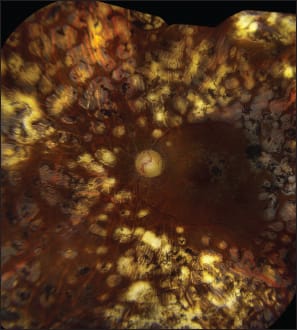

Because of persistent dense vitreous hemorrhage, he underwent pars plana vitrectomy OD two years earlier at an outside medical center. His best-corrected visual acuity on initial examination was 20/25 in both eyes. A giant retinal tear was noted from 8 o'clock to 12 o'clock in the peripheral retina of the right eye (Figure 1).

Figure 1. A 41-year-old man with a history of PDR and PPV two years earlier presented with a giant retinal tear in the right eye. The giant retinal tear was rolled up and contracted and extended from 8 o'clock to 12 o'clock, demarcated posteriorly by extensive PRP. The macula was attached and stable with 20/25 visual acuity.

The giant retinal tear was well demarcated by the previous PRP and spared the macula. The foveal contour was normal on OCT. The patient has been observed for the past one-and-a-half years, and the associated retinal detachment has not progressed.